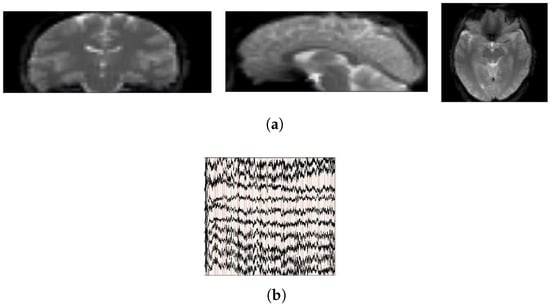

2.1. Principles of EEG–fMRI Neuroimaging

2.1.1. Principles of EEG Neuroimaging

2.1.2. Principles of fMRI Neuroimaging

2.2. Simultaneous EEG–fMRI Dataset

2.2.1. Resting-State Simultaneous EEG–fMRI Dataset

2.2.2. Task-Based Simultaneous EEG–fMRI Dataset